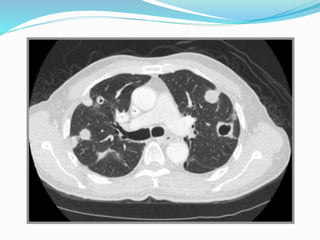

Cannon-ball metastases

 Commonest primary sites

being

 RCC

 Choriocarcinoma.

Cannon-ball metastases  Commonestprimary sites being  RCC  Choriocarcinoma.